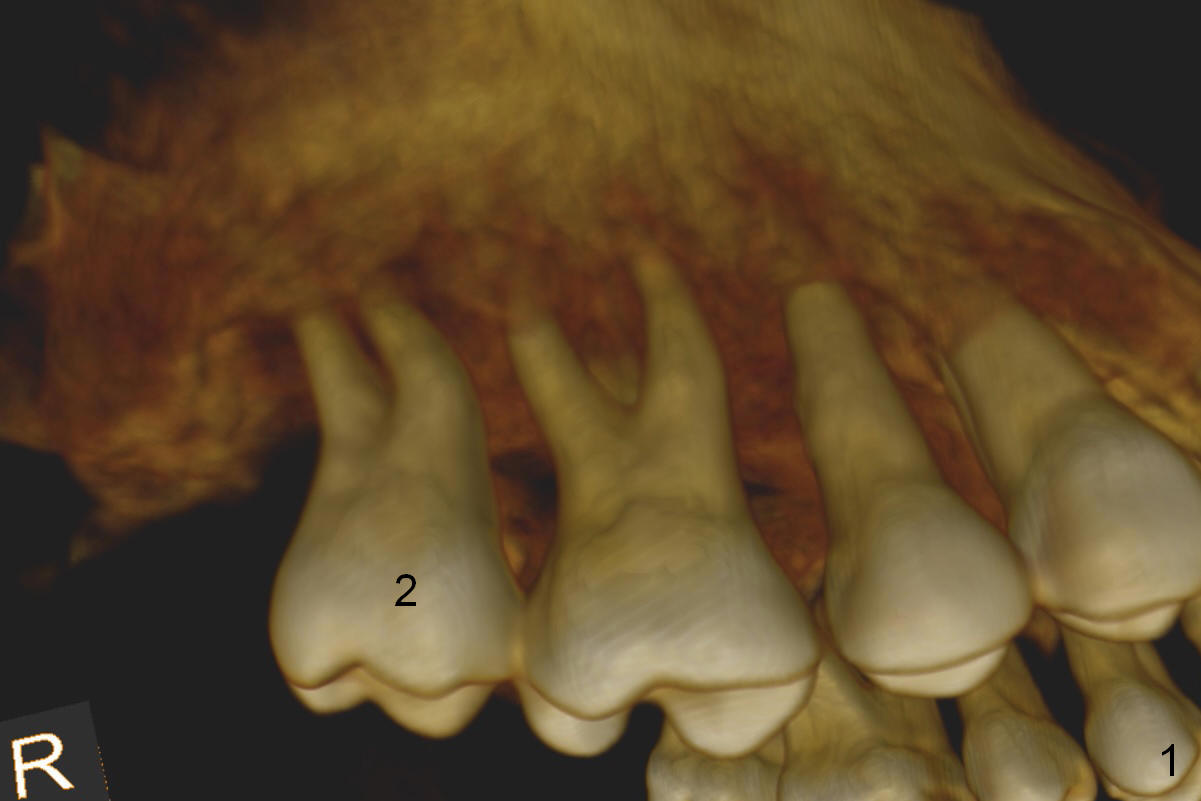

A 46-year-old lady is a typical dental phobic, but she is reasonable. Her chronic periodontitis is generalized and severe (Fig.1 3-D image, taken 1 year ago). An implant has been placed at #6 (healed site). It fails for the first time, probably due to bone loss after extraction. Soon after last periodontal maintenance, the tooth #2 develops pain and swelling. Immediate implant is a must.

The socket is wider buccopalatally (Fig.2 (3-D disto-occlusal view),3 (coronal section)) than mesiodistally (Fig.1,4 (sagittal section),5 (axial section)). Unless more bone loss has occurred in the last year, a 6x10 mm UF implant is to be placed in the middle of the socket (Fig.6, (soaked with 2% Xylocaine/1:50,000 Epinephrine gauze)) with bone graft to be placed in the buccal and palatal gaps (red circles). Bone density in the middle of the socket is 550-700 Hounsfield units. Use RT2 or 2 mm pilot drill to start osteotomy ~ 3 mm. The largest osteotome is RT4, or largest reamer 4 mm, followed by 4.5x17 mm tap at 14 mm, until 6x17 mm one. Make sure that the sinus floor is penetrated.